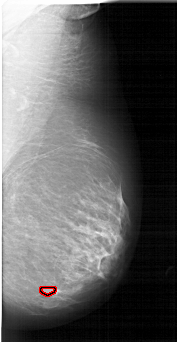

A_1739_1.RIGHT_MLO

RIGHT_MLO LINES 6496 PIXELS_PER_LINE 3346 BITS_PER_PIXEL 12 RESOLUTION 43.5 OVERLAY

FILE: A_1739_1.RIGHT_MLO.OVERLAY

TOTAL_ABNORMALITIES 1

ABNORMALITY 1

LESION_TYPE MASS SHAPE LOBULATED MARGINS CIRCUMSCRIBED

ASSESSMENT 3

SUBTLETY 1

PATHOLOGY BENIGN

TOTAL_OUTLINES 1

BOUNDARY